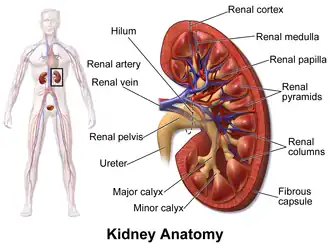

The kidneys lie in the retroperitoneal space behind the abdomen, and act to filter blood to create urine | |

In humans, the kidneys are two reddish-brown bean-shaped blood-filtering organs[1] that are a multilobar, multipapillary form of mammalian kidneys, usually without signs of external lobulation.[2][3] They are located on the left and right in the retroperitoneal space, and in adult humans are about 12 centimetres (4+1⁄2 inches) in length.[4][5] They receive blood from the paired renal arteries; blood exits into the paired renal veins. Each kidney is attached to a ureter, a tube that carries excreted urine to the bladder.

Structure

In humans, the kidneys are located high in the abdominal cavity, one on each side of the spine, and lie in a retroperitoneal position at a slightly oblique angle.[9] The asymmetry within the abdominal cavity, caused by the position of the liver, typically results in the right kidney being slightly lower and smaller than the left, and being placed slightly more to the middle than the left kidney.[10][11][12] The left kidney is approximately at the vertebral level T12 to L3,[13] and the right is slightly lower. The right kidney sits just below the diaphragm and posterior to the liver. The left kidney sits below the diaphragm and posterior to the spleen. On top of each kidney is an adrenal gland. The upper parts of the kidneys are partially protected by the 11th and 12th ribs. Each kidney, with its adrenal gland is surrounded by two layers of fat: the perirenal fat present between renal fascia and renal capsule and pararenal fat superior to the renal fascia.

The human kidney is a bean-shaped structure with a convex and a concave border.[14] A recessed area on the concave border is the renal hilum, where the renal artery enters the kidney and the renal vein and ureter leave. The kidney is surrounded by tough fibrous tissue, the renal capsule, which is itself surrounded by perirenal fat, renal fascia, and pararenal fat. The anterior (front) surface of these tissues is the peritoneum, while the posterior (rear) surface is the transversalis fascia.

The functional substance, or parenchyma, of the human kidney is divided into two major structures: the outer renal cortex and the inner renal medulla. Grossly, these structures take the shape of eight to 18 cone-shaped renal lobes, each containing renal cortex surrounding a portion of medulla called a renal pyramid.[18] Between the renal pyramids are projections of cortex called renal columns.

The tip, or papilla, of each pyramid empties urine into a minor calyx; minor calyces empty into major calyces, and major calyces empty into the renal pelvis. This becomes the ureter. At the hilum, the ureter and renal vein exit the kidney and the renal artery enters. Hilar fat and lymphatic tissue with lymph nodes surround these structures. The hilar fat is contiguous with a fat-filled cavity called the renal sinus. The renal sinus collectively contains the renal pelvis and calyces and separates these structures from the renal medullary tissue.[19]